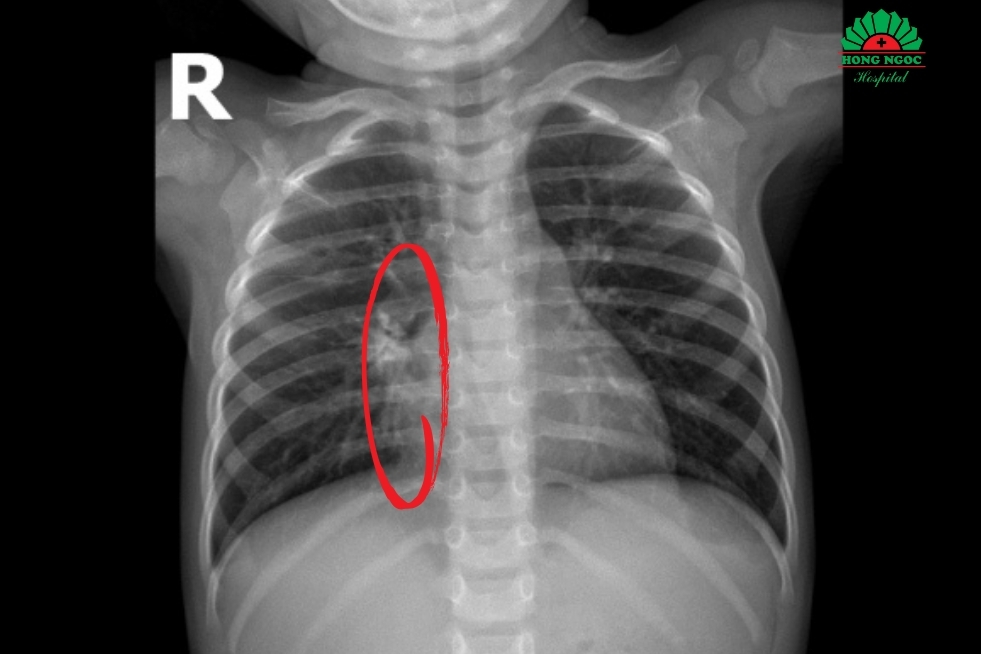

Kết quả chụp CT lồng ngực cho thấy tổn thương nghiêm trọng tại phổi phải với hình ảnh viêm phổi hoại tử, kích thước ổ tổn thương 40 x 42 x 20 mm, chiếm khoảng 1/4 thể tích phổi phải. Trẻ đồng thời có tràn dịch màng phổi hai bên dày khoảng 11 mm và xẹp hoàn toàn hai thùy dưới của phổi. Kết quả nội soi tai mũi họng ghi nhận viêm tai giữa ứ mủ hai bên. Các xét nghiệm vi sinh cho thấy test nhanh RSV dương tính, cấy dịch tỵ hầu phát hiện phế cầu, và PCR dịch tỵ hầu dương tính với HI, phế cầu và Mycoplasma IgM.

Kết quả CT và siêu âm ngực cho thấy bé N.P bị hoại tử phổi phải kích thước 40×42×20 mm kèm tràn dịch màng phổi hai bên, dày 11 mm.